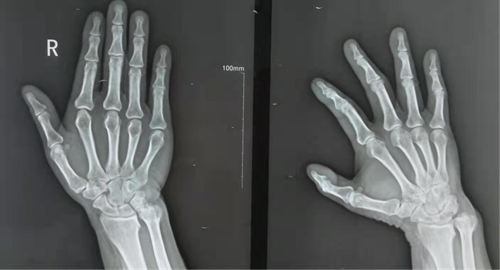

通过右腕关节X线及MRI等相关检查,手外科主任潘俊博诊断其为右侧下尺桡关节骨性关节炎。考虑患者的术后功能要求及年龄,手外科医师们集体讨论,最终决定为患者实施Sauve-Kapandji术。

术中,患者尺骨头、下尺桡关节面及尺骨远端暴露。在经过去除下尺桡关节周围炎性滑膜组织及关节面软骨、距尺骨关节面约1.5 cm处截断尺骨、正确摆放尺骨头相对于桡骨乙状切迹的位置、将截断尺骨中的松质骨移植于下尺桡关节后。潘俊博及其团队通过C臂机透视,确认尺骨头位置良好后,在患者尺骨上拧入空心加压螺钉和克氏针固定、融合下尺桡关节,并将患者尺侧屈腕肌及尺侧伸腕肌腱的一半悬吊、固定于尺骨近段,以防止远期发生尺骨近端与桡骨撞击所产生的疼痛感。